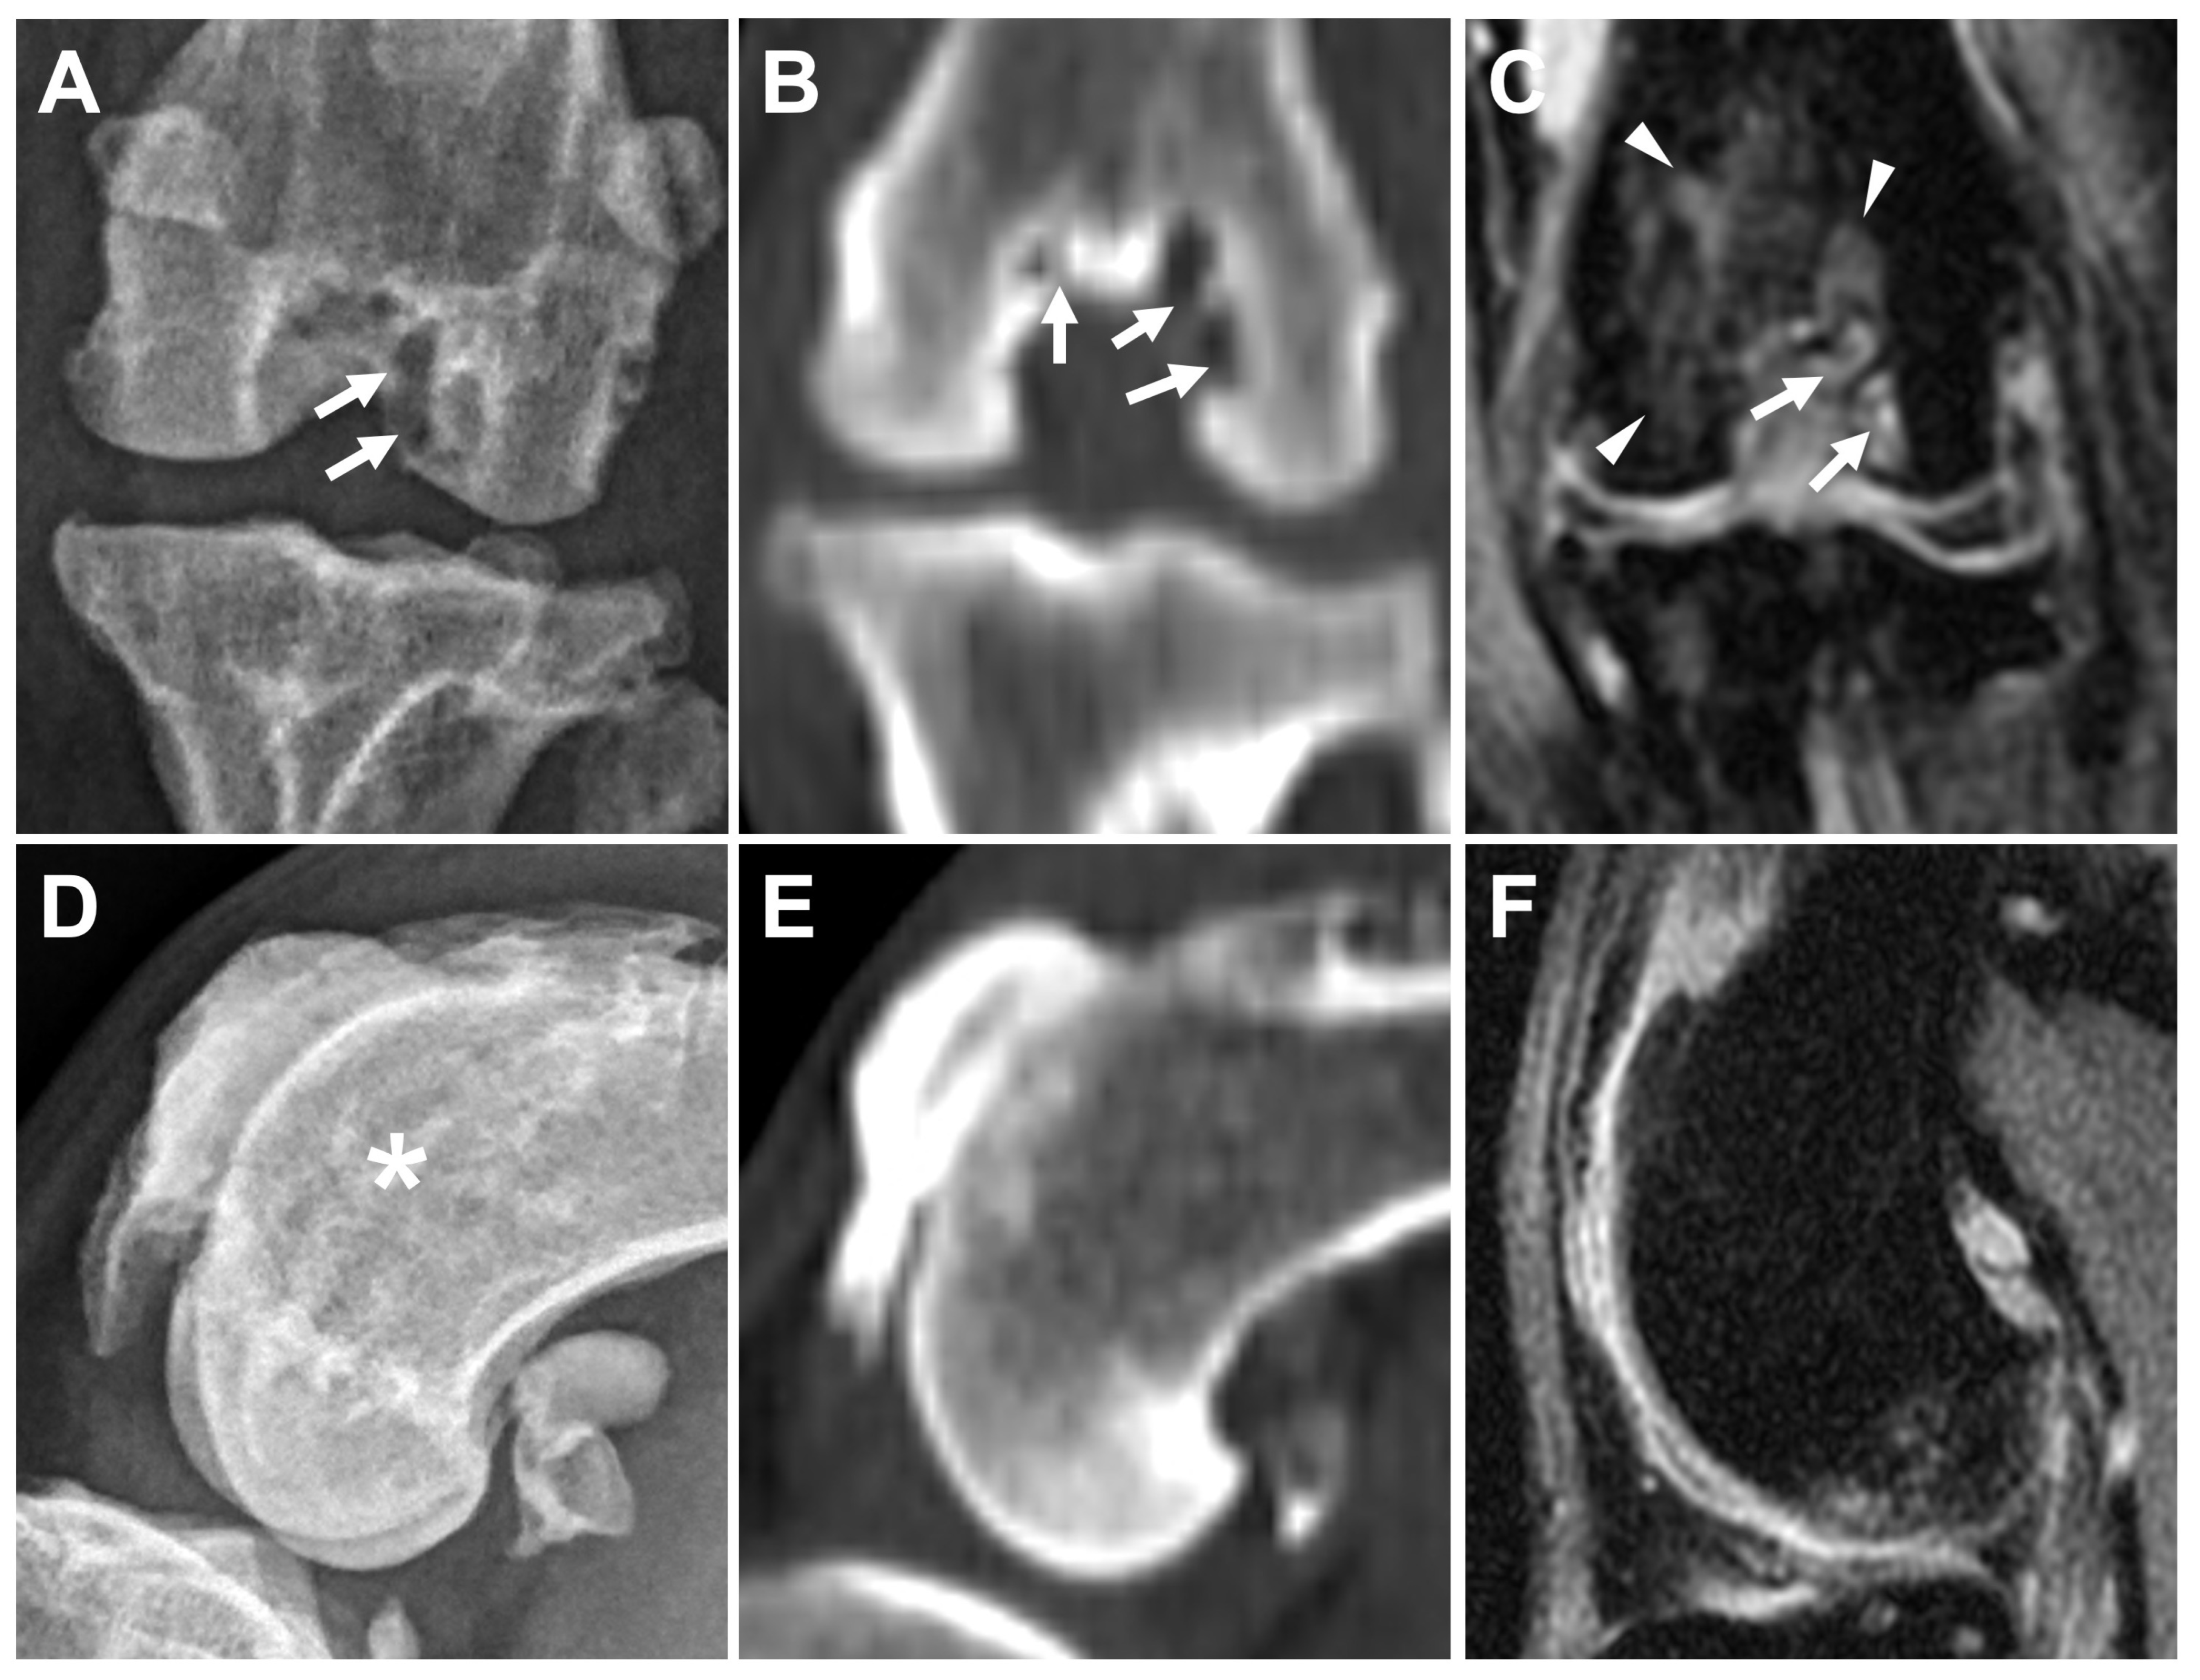

3.2.4. Subchondral Bone Lesions

3.2.5. Meniscal and Cartilage Lesions